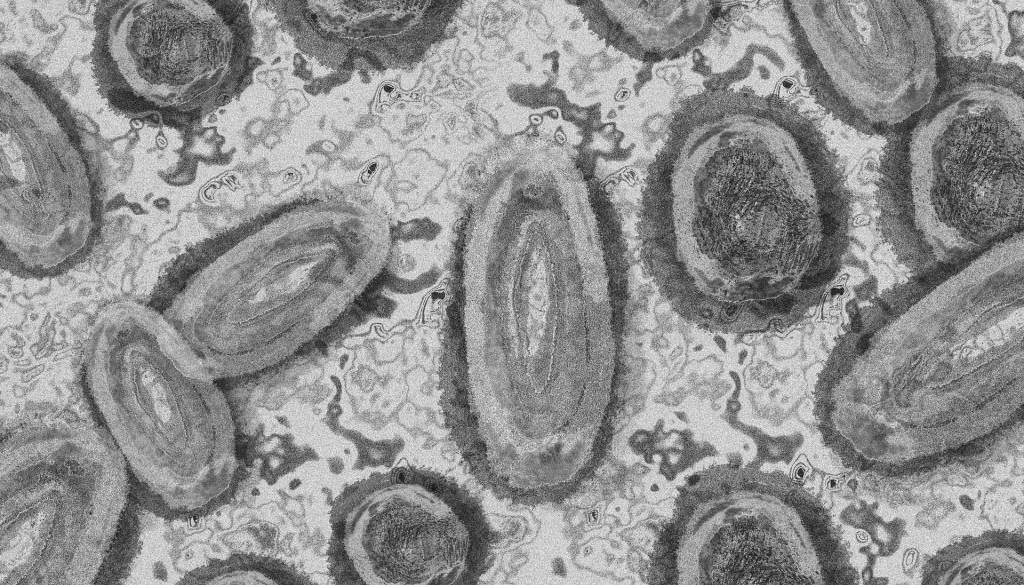

Opičje koze so redka bolezen, ki jo povzroča okužba z virusom opičjih koz. Omenjeni virus spada v rod ortopoksvirusov, ki med drugim vključuje tudi virus variole, ki povzroča črne koze, virus vakcinije, ki se uporablja v cepivu proti črnim kozam in virus kravjih koz.